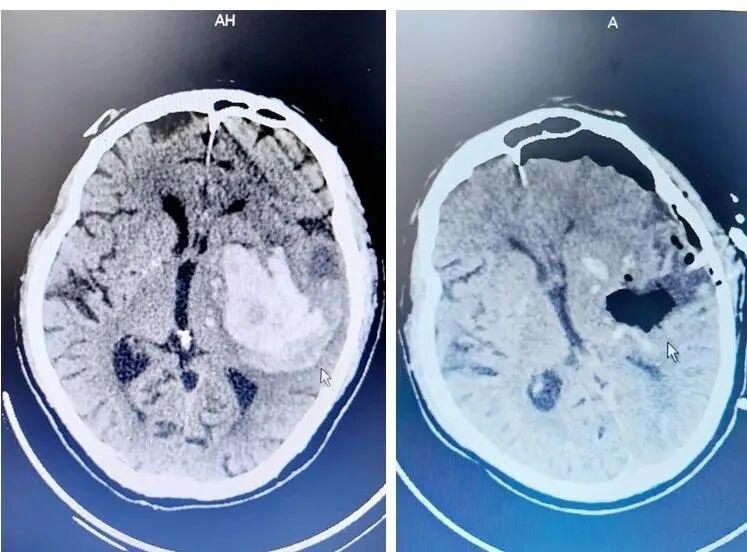

【“組團(tuán)式”幫扶】惠州三院醫(yī)療幫扶隊(duì)員在冊(cè)亨縣人民醫(yī)院利用小骨窗內(nèi)鏡技術(shù)點(diǎn)亮腦出血患者生命曙光